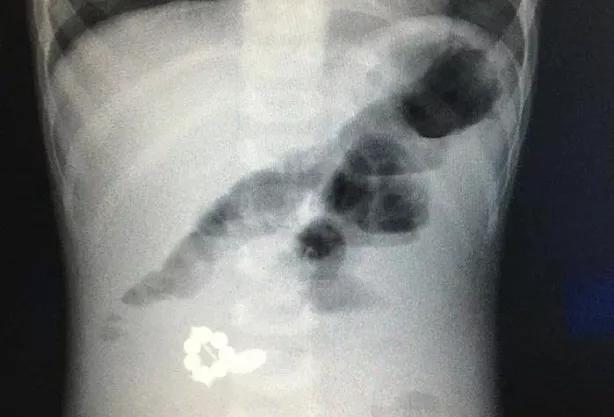

Ребенок поступил в детскую областную клиническую больницу с жалобами на рвоту, вялость и повышенную температуру. После рентгена выяснилось, что в брюшной полости маленького пациента находятся семь магнитов и одна батарейка, что привело к кишечной непроходимости.

Врачам пришлось провести полуторачасовую операцию, чтоб извлечь инородные предметы из тела малыша. Сейчас мальчик чувствует себя хорошо и уже готовится к выписке.

Фото: министерство здравоохранения Тульской области